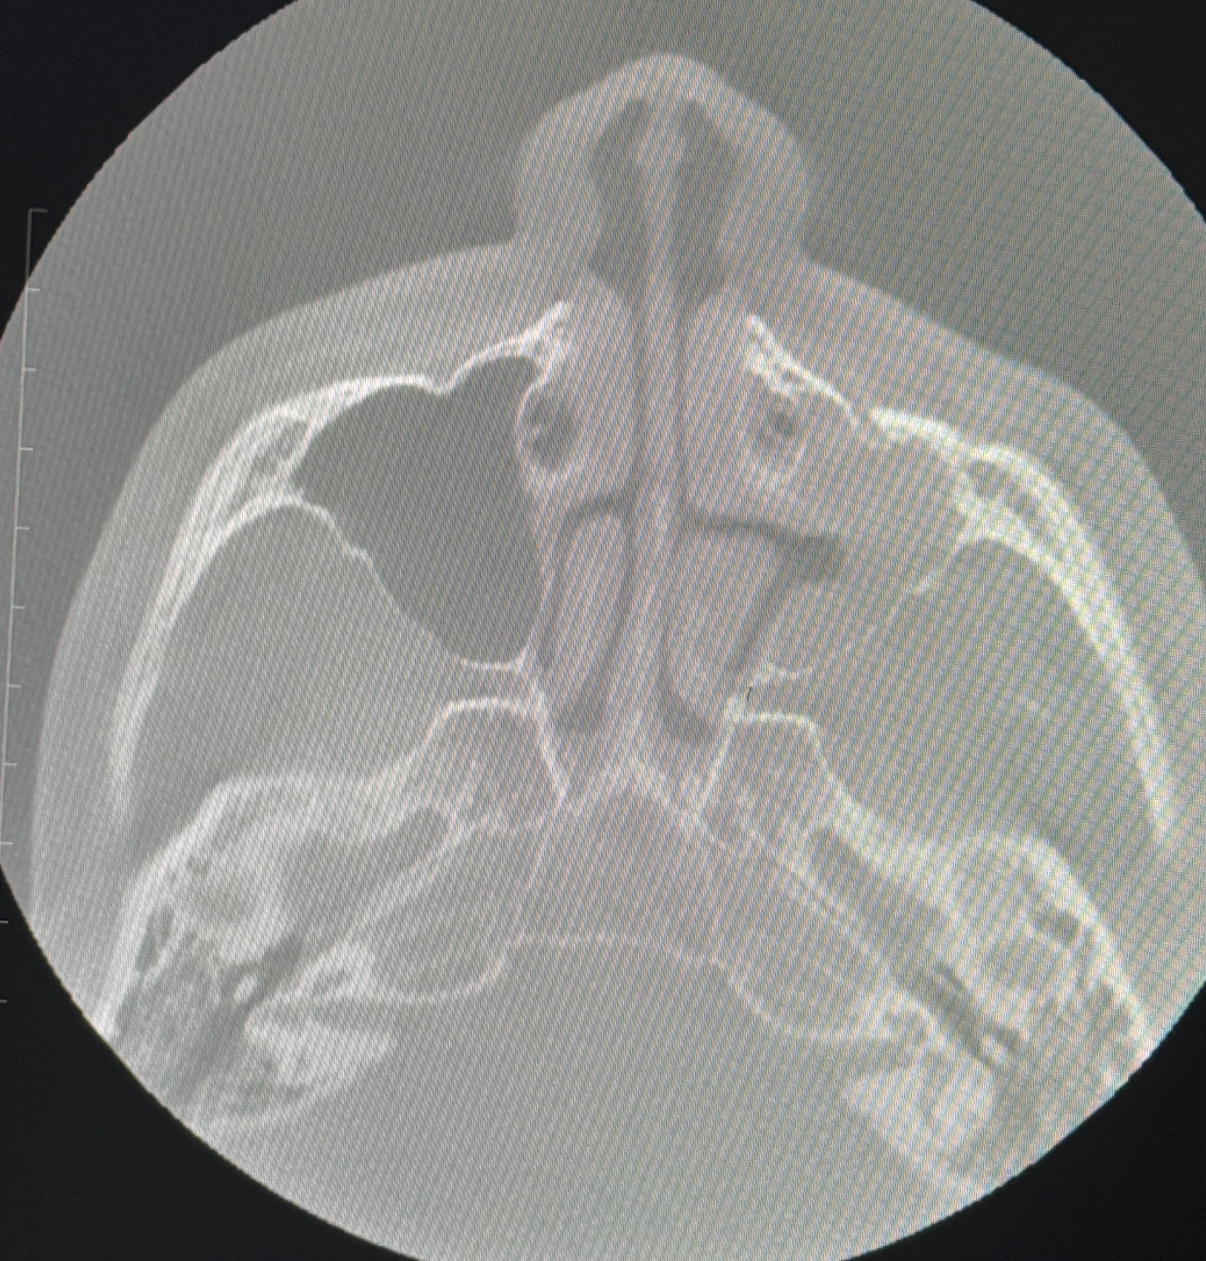

IMG 4586

Here’s an x- ray I was diagnosed with maxillary sinus hypoplasia ( one side is black other is white) can anyone tell if theirs any more deformities? Also for reference if I do try to get lefort one my palate is 35.3 mm for UR6, I shave wisdom teeth also coming in and sleep apnea test results will be sons what surgery should I plan for I also am asymmetrical .